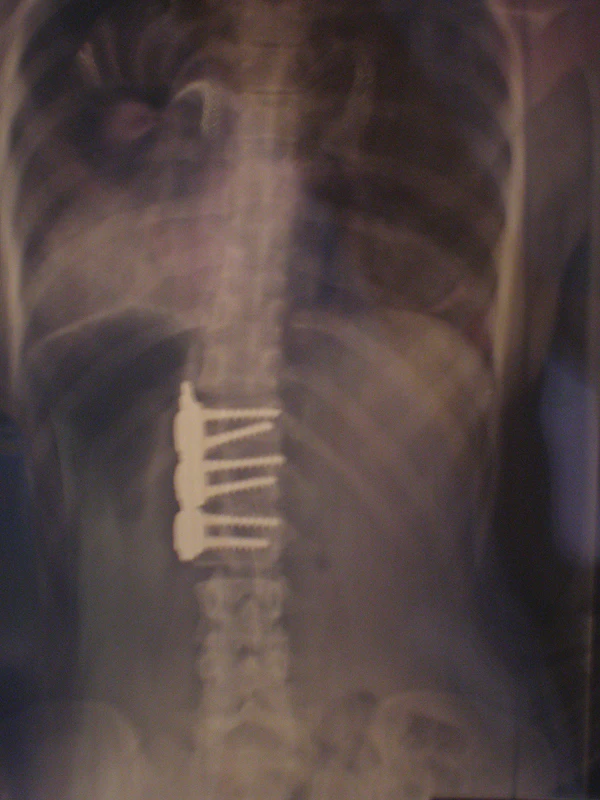

При оперативном лечении искривлённая часть позвоночника выпрямляется до определённого возможного угла при помощи металлических стержней и шурупов (т. н. педикулярных винтов), что ведёт к обездвиживанию этих отделов позвоночника. Операция при сколиозе подходит прежде всего для сильных искривлений, которые больше не могут лечиться другими методами. Оперативная фиксация может предотвратить дальнейшую прогрессию и ухудшение состояния.

Оперативный разрез при заднем доступе находится на средней линии туловища и одном из крыльев тазовой кости. Используются различные системы металлических стержней, которые крючками или шурупами (т. н. педикулярными винтами) прикрепляются к позвоночнику и затем изменяют его кривизну на больших участках. Для лучшей стабилизации всей конструкции стержни имеют поперечные соединения (мостики).

Для коррекции в определённых сегментах удаляют диски и сбоку в корригируемые позвонки вводят шурупы. Их соединяют стержнем и после коррекции прикрепляют к нему. На место вынутых дисков вводят подготовленный костный материал. При современной методике операции для лучшей стабильности применяют два стержня, если это позволяет состояние позвоночника[6].